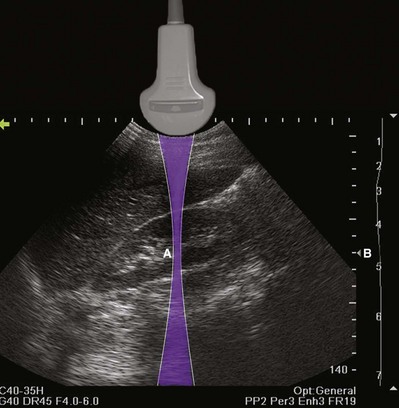

The resolution of an ultrasound image refers to the ability to discriminate two objects in close proximity to one another. Axial resolution refers to the ability to identify as separate two objects in the direction of the traveling sound wave. Axial resolution is directly dependent on the frequency of sound waves. The higher the sound wave’s frequency is, the better the axial resolution. Lateral resolution refers to the ability to identify separately objects that are equidistant from the transducer. Lateral resolution is a function of the focused width of the ultrasound beam and is a characteristic of the transducer. The location of the narrowest beam width can be adjusted by the user. The more focused the beam is, the better the lateral resolution at that location. Thus image quality can be enhanced by locating the narrowest beam width (focus or focal zone) at the depth of the object or tissue of interest (Fig. 4–15).

Figure 4–15 The shape of the ultrasound beam is simulated in this drawing (purple). The focal zone (A) is located to produce the best lateral resolution of the medial renal cortex. The location of the focal zone is designated by the caret (B). The location of the focal zone can be adjusted by the operator.